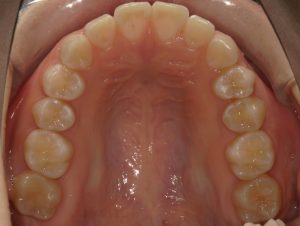

治療前→治療後(上顎)

親知らずを抜いたスペースを利用して左上の第二大臼歯を後ろに動かし、第一大臼歯を外側に移動させました。